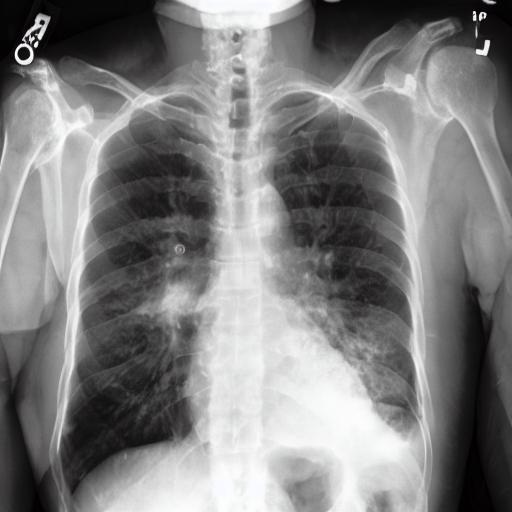

Medical imaging uses advanced technologies to visualise internal parts of the body. These include X-rays, magnetic resonance imaging (MRI) scans, computed tomography (CT) scans, positron emission tomography (PET) scans, ultrasounds and more.

“Together, you identify a problem that needs solving. Maybe you want to diagnose COVID-19 from chest X-rays, for instance,” Aaron said.